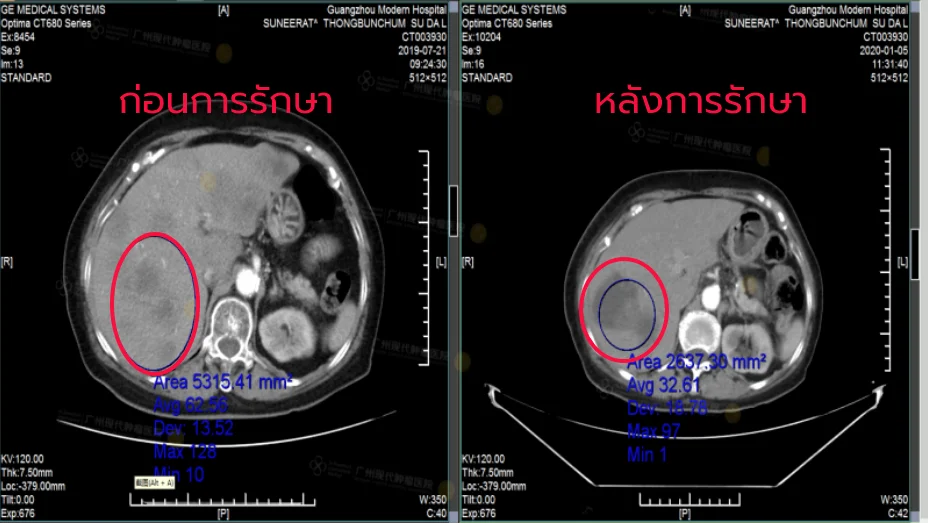

โรงพยาบาลมะเร็งสมัยใหม่กว่างใช้วิธีการรักษามะเร็งแบบใหม่ “การแพทย์ผสมผสานระหว่างจีนกับตะวันตก และการผ่าตัดแบบบาดแผลเล็ก” โดยใช้ทคนิค เช่น การรักษาแบบคีโมเฉพาะจุด การฝังรังสี การใช้มีดคังโป การจี้ด้วยคลื่นไมโครเวฟ มีดนาโน และการรักษาด้วยความเย็น ซึ่งจะมีการวางแผนการรักษาเฉพาะบุคคลตามสภาพร่างกายและความต้องการของผู้ป่วยด้วยเทคนิคการรักษาแบบบาดแผลเล็ก

การเปรียบเทียบประสิทธิภาพ

| อัตราการรอดชีวิต 5 ปี | 75% | 92% |

| อัตราการเก็บรักษาเต้านม | 30% | 85% |

| ผลข้างเคียงระดับ 3 ขึ้นไป | 35% | 8.7% |